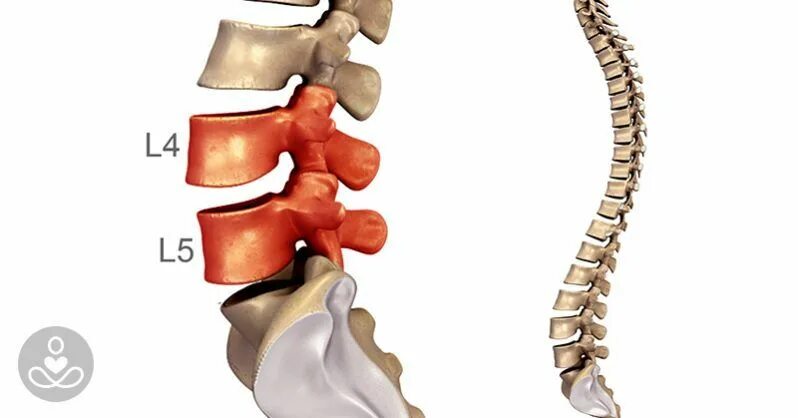

Сегмент l1 l5